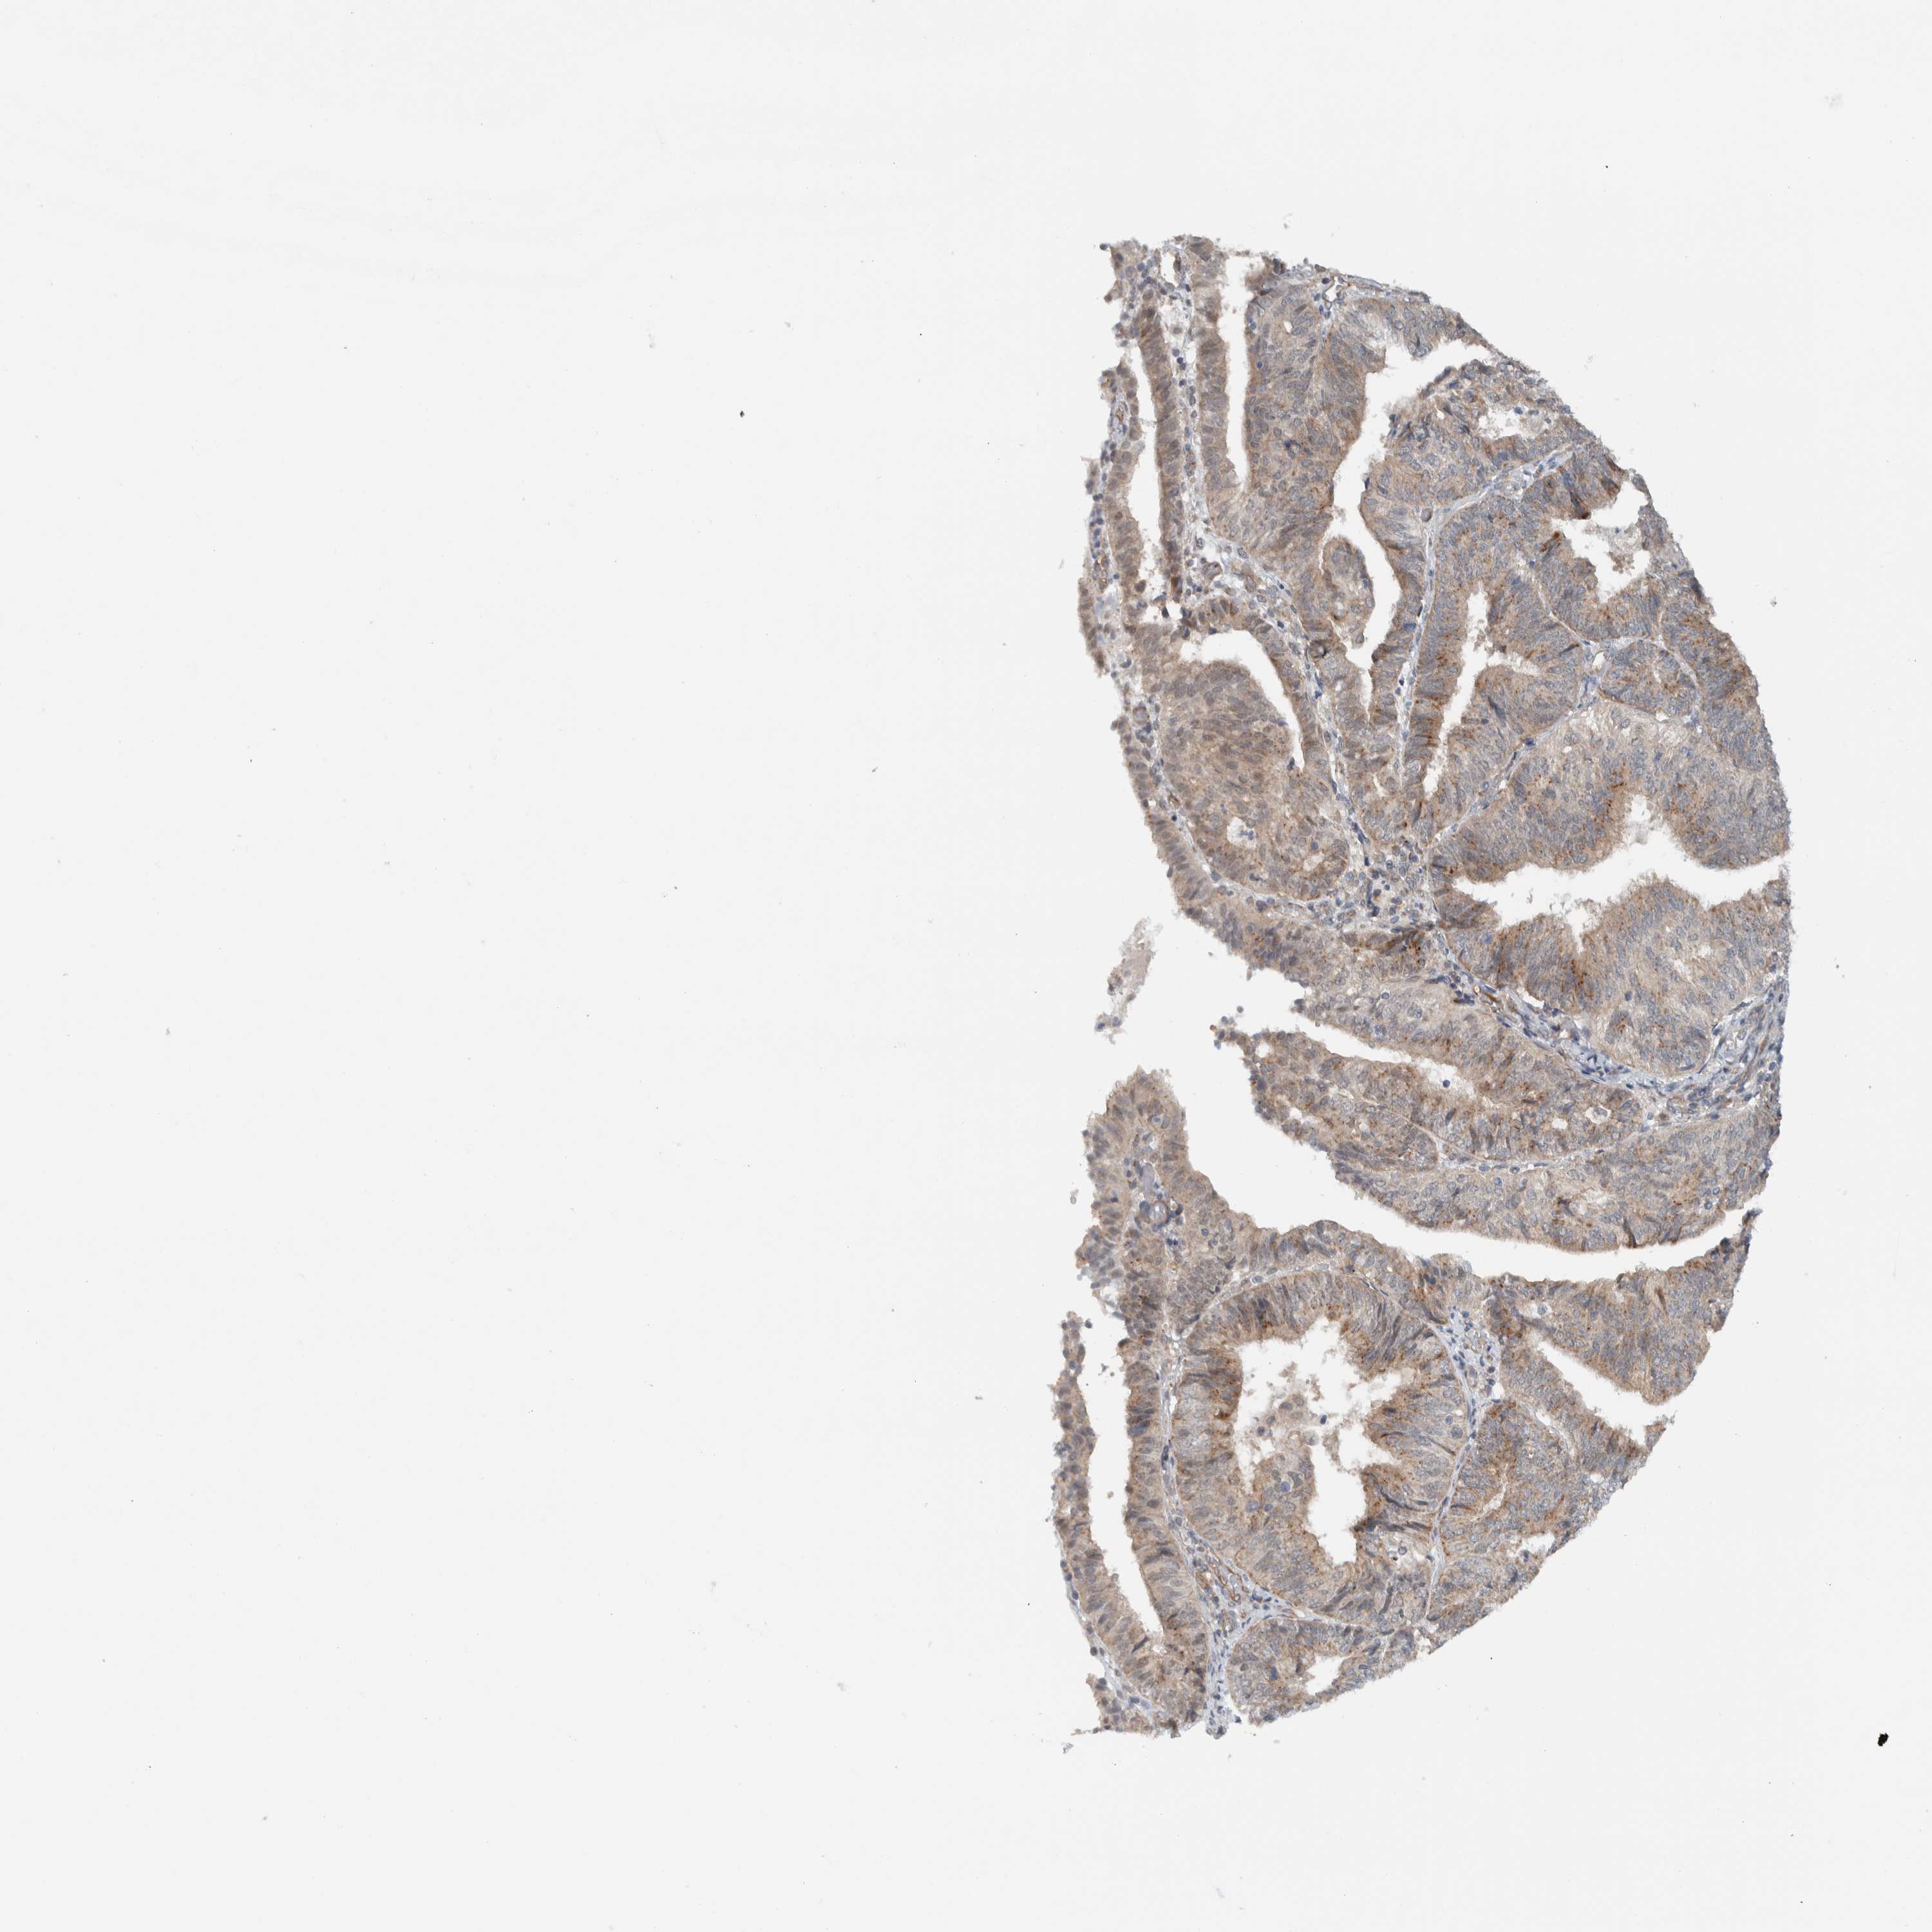

ENDOMETRIAL CANCER - Protein expressioni

A mouse-over function shows sample information and annotation data. Click on an image to view it in a full screen mode. Samples can be filtered based on level of antibody staining by selecting one or several of the following categories: high, medium, low and not detected. The assay and annotation is described here.

Note that samples used for immunohistochemistry by the Human Protein Atlas do not correspond to samples in the TCGA dataset.

Antibody stainingi

Antibody staining in the annotated cell types in the current human tissue is reported as not detected, low, medium, or high, based on conventional immunohistochemistry profiling in selected tissues. This score is based on the combination of the staining intensity and fraction of stained cells.

Each image is clickable and will lead to virtual microscopy that enables deeper exploration of all samples and also displays staining intensity scores, fraction scores and subcellular localization as well as patient and tissue information for each sample.

Antibody HPA024093

Staining

High

Medium

Low

Not detected

Intensity

Strong

Moderate

Weak

Negative

Quantity

>75%

75%-25%

<25%

None

Location

Nuclear

Cytoplasmic/membranous

Cytoplasmic/membranous,nuclear

Adenocarcinoma, NOS